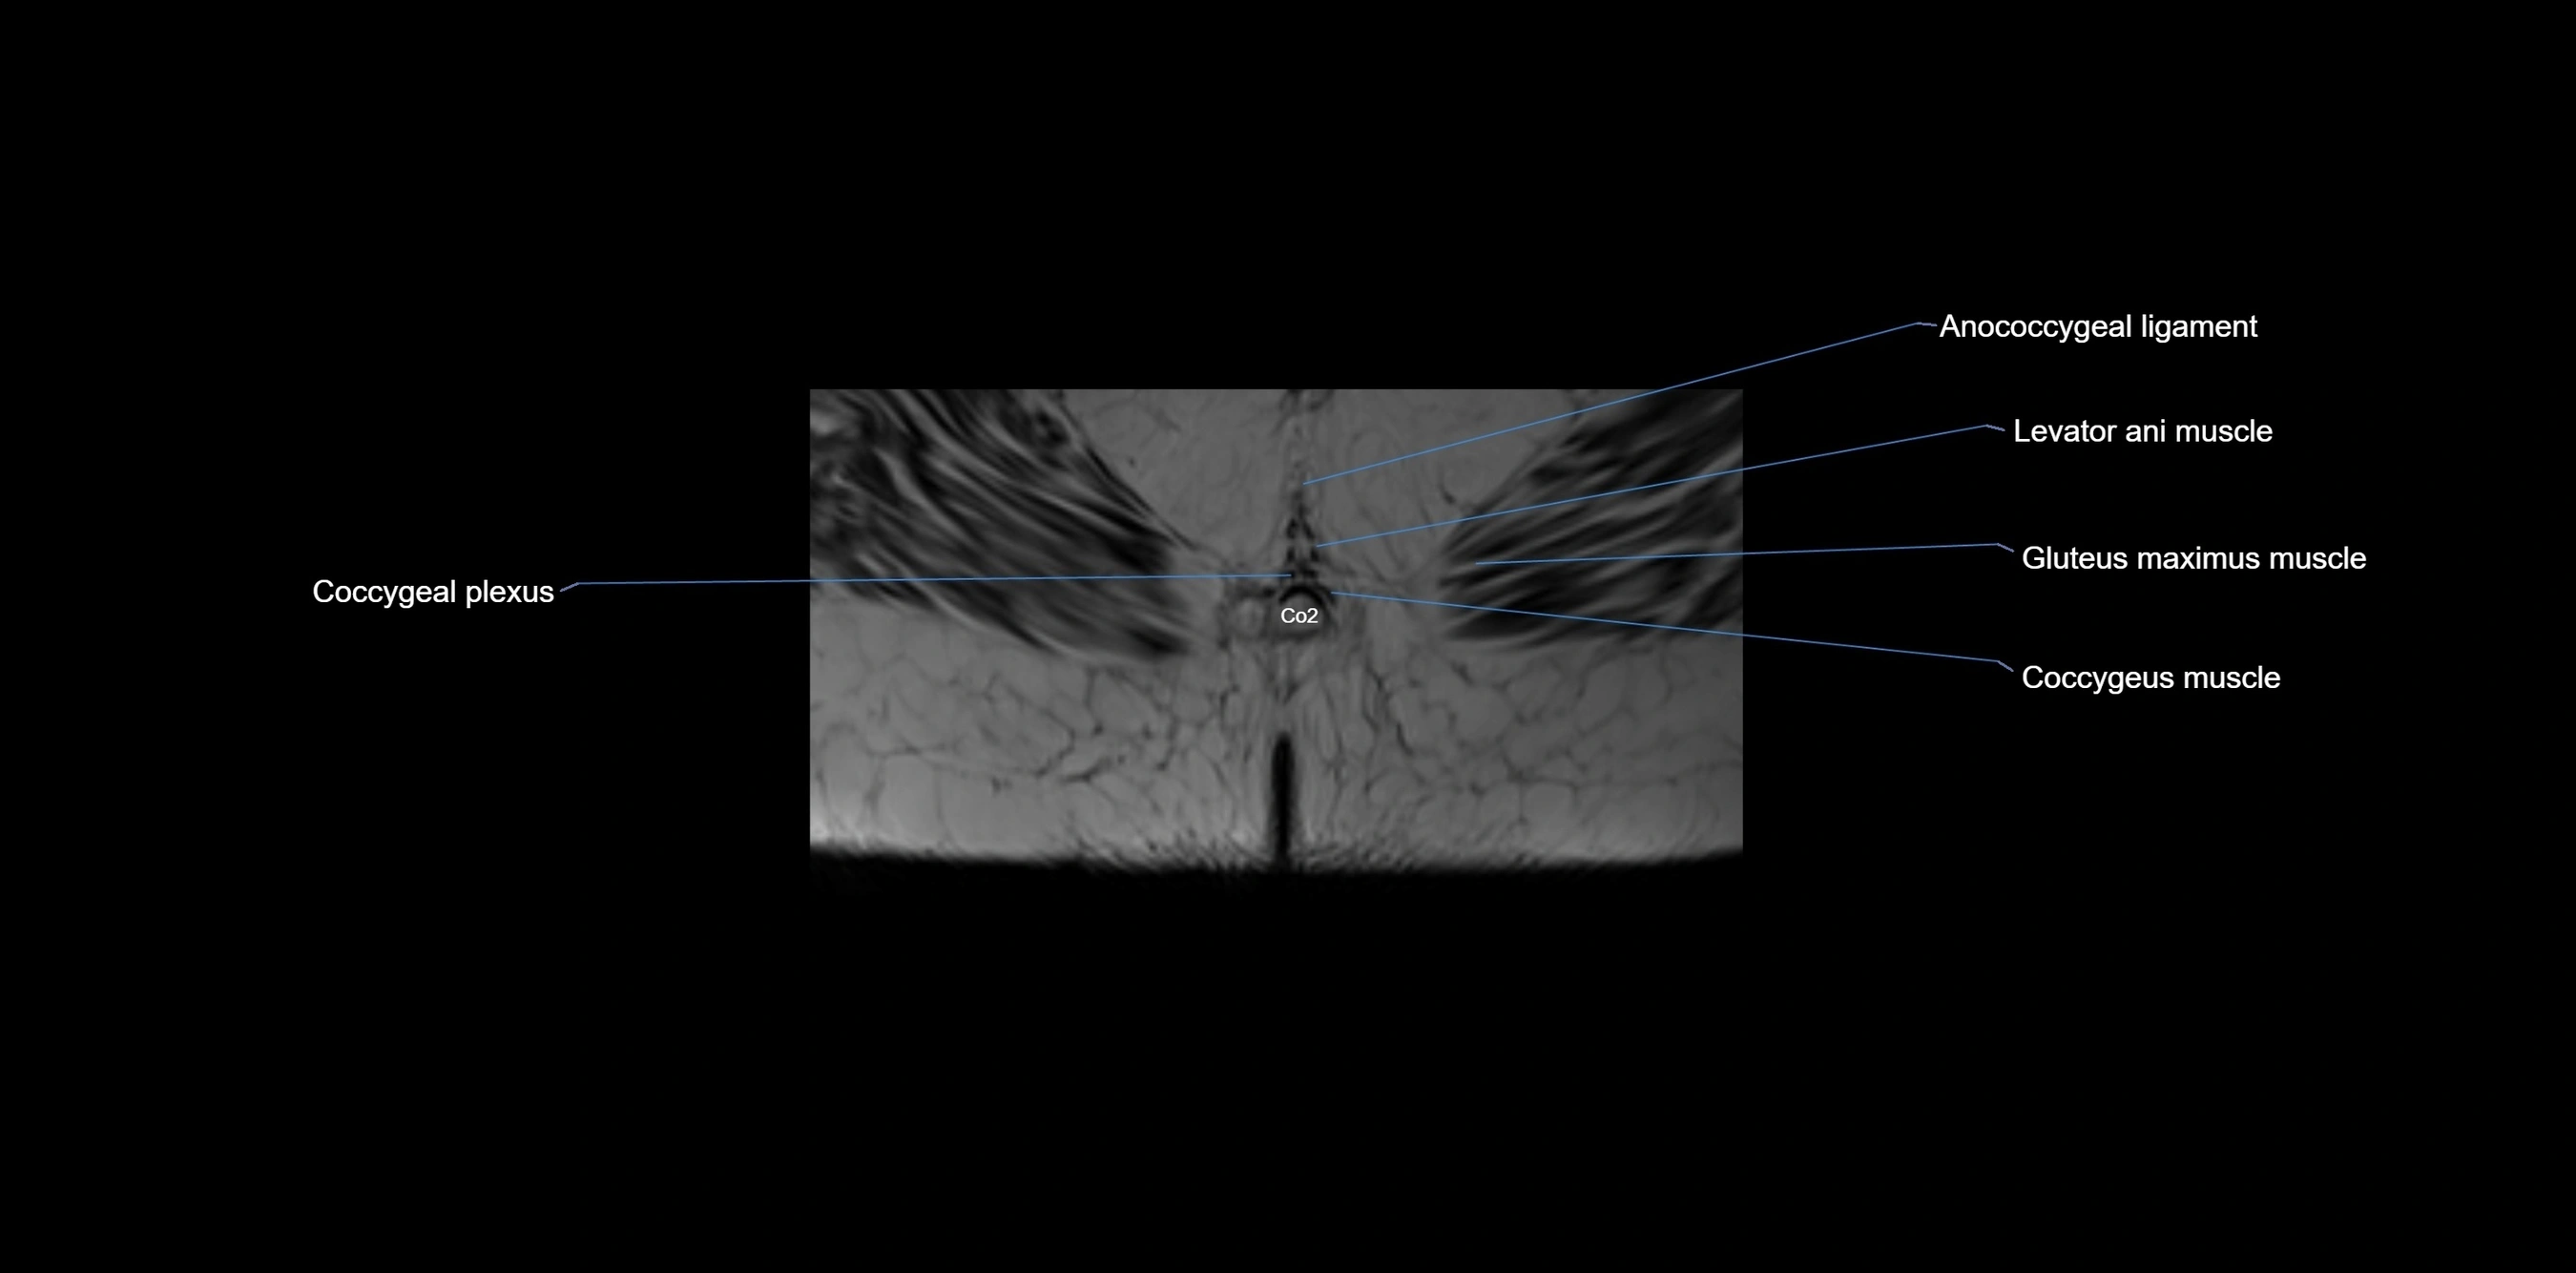

MRI image

image